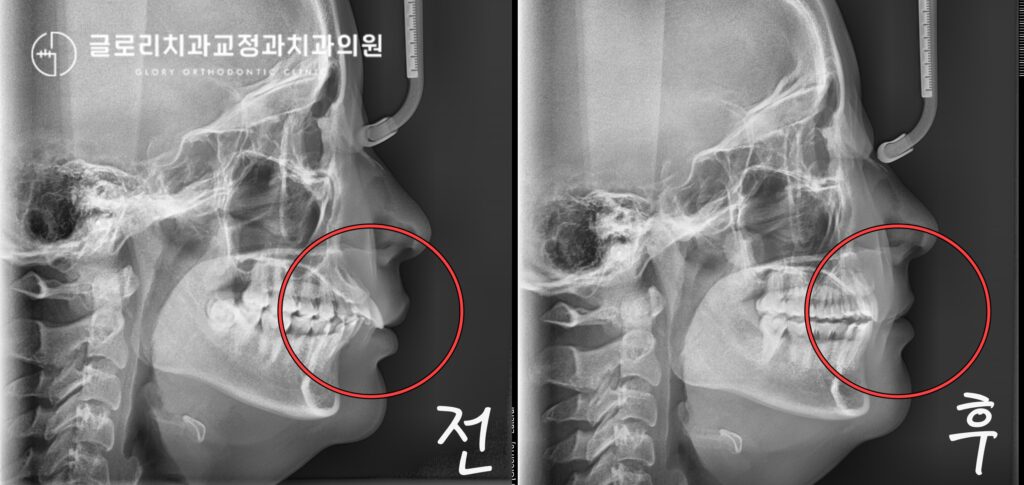

중랑구 교정치과 앞니가 삐뚤고 입이 나와보인다면? 발치교정을 통한 골격성 2급부정교합 개선 가능합니다.

안녕하세요, 교정과 전문의 김정은입니다. 앞니는 단순히 음식을 자르는 기능을 넘어 첫인상을 결정짓는 중요한 심미요소를 담당하는 부위입니다. 특히나 웃을때 제일 먼저…